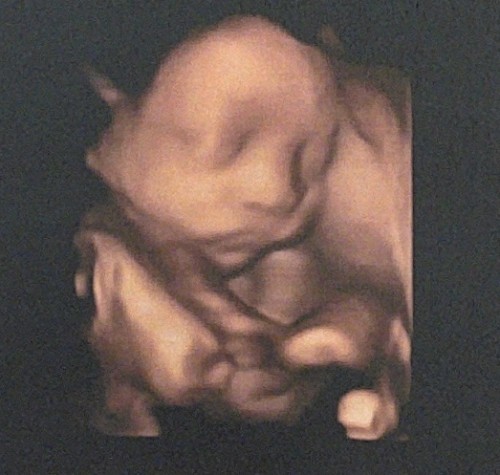

มีแม่บ้านไหนไป ultrasound แล้วพบว่าสายสะดือพันรอบคอน้องอยู่เหมือนบ้านนี้มั้ยคะ ตอนนี้พันรอบคออยู่ 1 รอบ แต่คุณหมอบอกว่าโดยรวมยังปกติอยู่ น้ำหนักตามเกณฑ์ หัวใจเต้นตามปกติ ไม่ทราบว่าบ้านไหน มีอาการนี้แล้วสายสะดือคลายจากคอน้องไปเองบ้างมั้ยคะ ตอนนี้คุณหมอให้นับลูกดิ้นอยู่ค่ะ (ยังดิ้นเป็นปกติ) #ท้องแรกค่ะ #28w